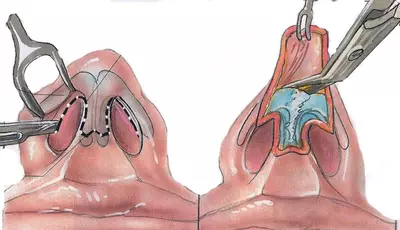

Rinoplastastiya, qoida tariqasida, umumiy behushlik ostida amalga oshiriladi. Operatning davomiyligi ishning murakkabligi va hajmiga bog'liq, o'rtacha 1-2 soat. Manifoulyatsiya texnikasi estetik muammoga qarab jarroh tomonidan tanlanadi. Ochiq va yopiq (endonazal) rinoplastika. Yopiq rinoplastika - operatsiya izisiz!

Yopiq rinoplastika - bu ichki bo'shliqda, tashqi teriga ta'sir qilmasdan, ichki teriga ta'sir qilmasdan, ichki terining tashqi terisi orqali olib boriladi va operatsiyadan keyingi tashqi tomondan qoldirilmagan.

Ochiq texnikani taqqoslash operatsiyadan keyingi izlarning yo'qligi.

Yopiq rinoplastika bilan burunmalardan biri bilan barcha anatomik tuzilmalarni burun va ochiq metodologiya bilan olib tashlash, burunning burunining tuzilishi bilan - burunning terisining "surish" bilan.

Teri tuzatish ochiq va yopiq bo'lganda, teri matolardan tozalaydi. Boshqacha qilib aytganda, to'qima travma nuqtai nazaridan ushbu ikki texnikaning farqi yo'q.

Rinoplastastiya, qoida tariqasida, umumiy behushlik ostida amalga oshiriladi. Operatning davomiyligi ishning murakkabligi va hajmiga bog'liq, o'rtacha 1-2 soat. Manifoulyatsiya texnikasi estetik muammoga qarab jarroh tomonidan tanlanadi. Ochiq va yopiq (endonazal) rinoplastika.